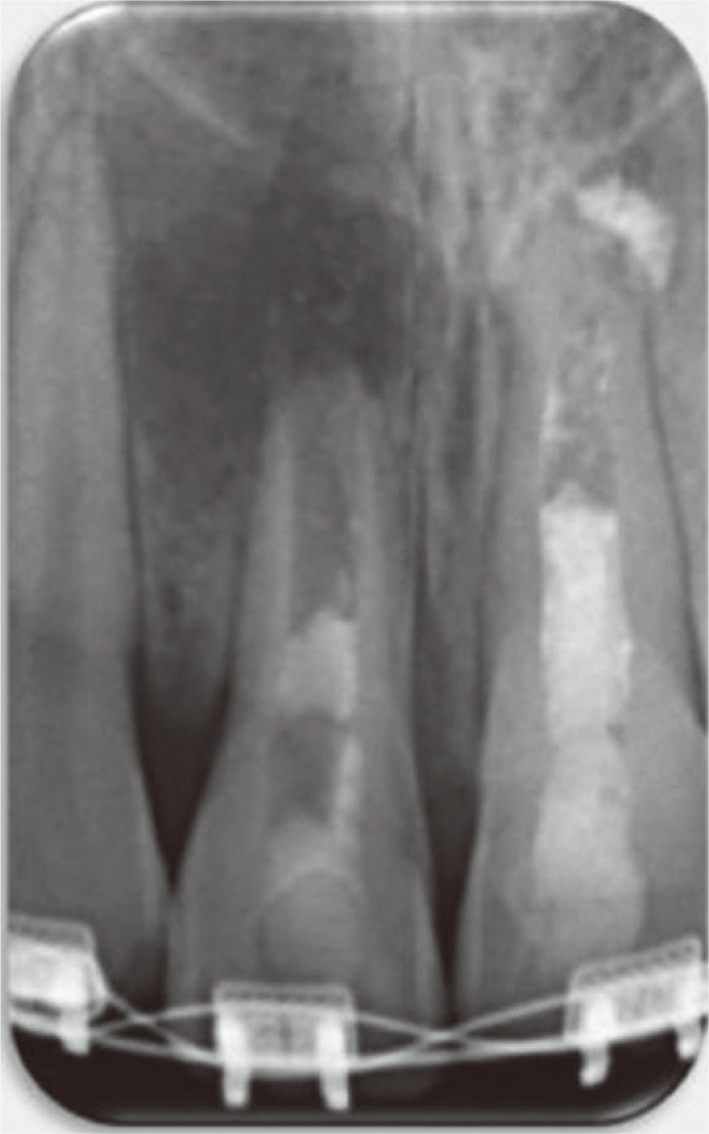

A 12 year old girl was referred from an orthodontic clinic to evaluate and treat the maxillary right central incisor (tooth #11). Her previous dental history was that the patient had trauma at age 9 years that affected her maxillary central incisors. She was referred by an orthodontist to a pedodontist in a private clinic to evaluate the traumatized teeth. An apexification was done for the maxillary left central incisor (tooth #21) using calcium hydroxide (Figure 1a) then she was referred back to her orthodontist who started the orthodontic treatment after one year. The patient developed buccal swelling one week after initiating the orthodontic treatment and the orthodontist sent the patient back to the pedodontist for the treatment on tooth #11. A regenerative endodontic retreatment was performed using MTA on tooth #11.

When this patient visited our clinic, she was an active orthodontic patient (Figure 1b). The tooth was asymptomatic and had a buccal sinus tract (Figure 1c). The medical history was unremarkable. Radiographic evaluation showed an immature open apex, with a large periradicular rarefaction and radiopaque material inside the root canal (Figure 1d). The intra-oral exam revealed an asymptomatic tooth #11 with an associated draining sinus tract. Clinical examination revealed no response to percussion and palpation tests. The tooth showed no mobility, and periodontal probing was within normal limits. The clinical diagnosis was previously treated asymptomatic periapical periodontitis.

Figure 1

(a) Diagnostic radiograph of the maxillary right central incisor (tooth #11) demonstrated incomplete root formation with diffuse periapical radiolucency and poor root canal filling; (b and c) Preoperative clinical photograph illustrates orthodontic treatment and the sinus tract related to tooth #11; (d) Periapical radiograph during orthodontic examination and before regenerative endodontic treatment that shows an open apex with apical rarefaction.

Figure 1 (a) Diagnostic radiograph of the maxillary right central incisor (tooth #11) demonstrated incomplete root formation with diffuse periapical radiolucency and poor root canal filling; (b and c) Preoperative clinical photograph illustrates orthodontic treatment and the sinus tract related to tooth #11; (d) Periapical radiograph during orthodontic examination and before regenerative endodontic treatment that shows an open apex with apical rarefaction.